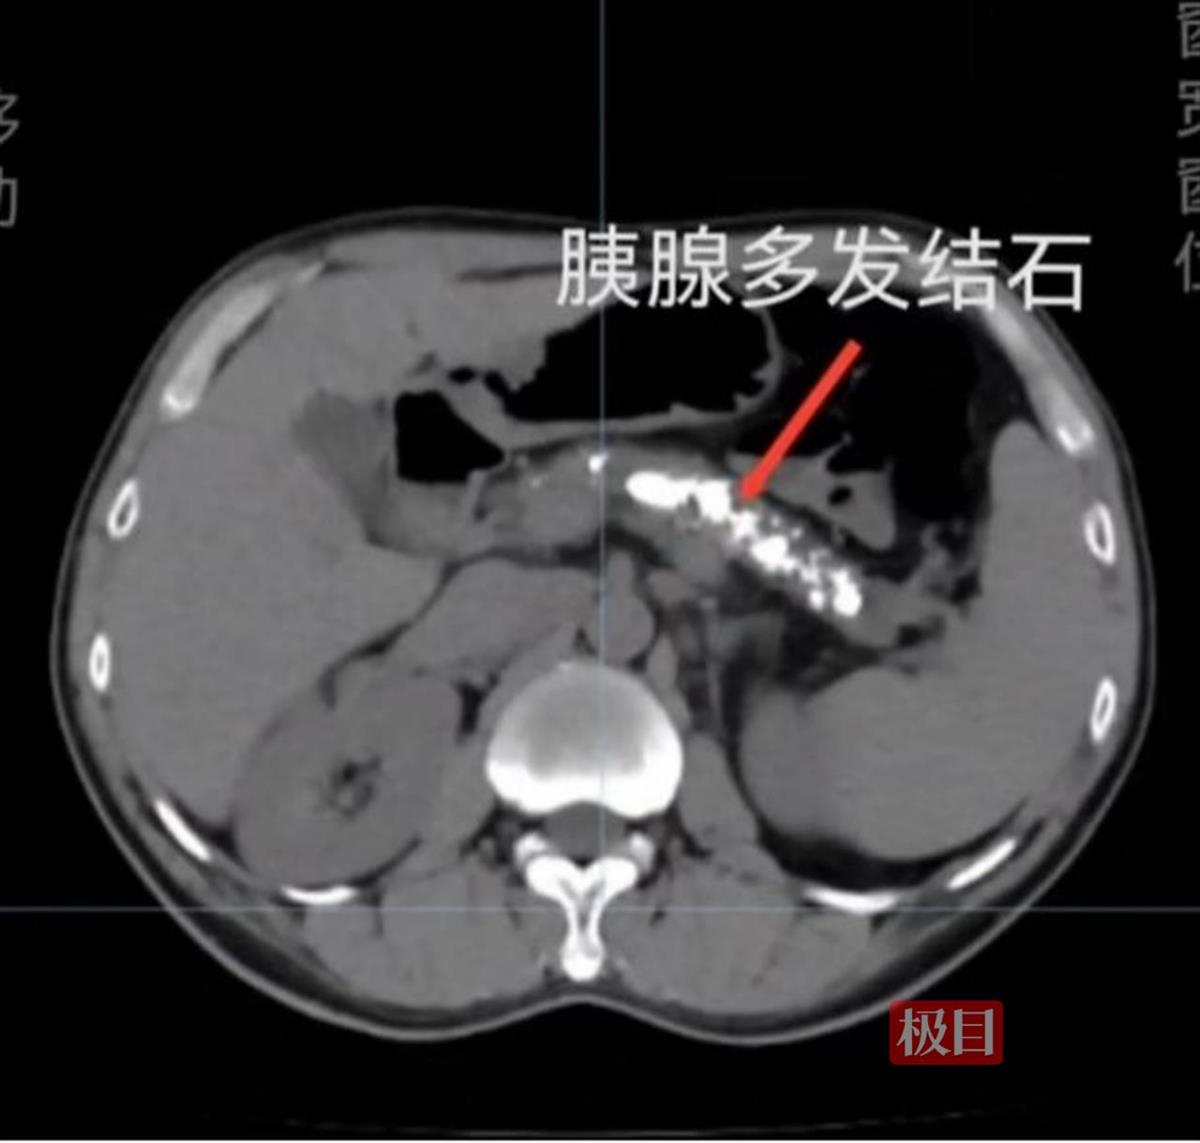

45岁的黄先生饮酒史已长达二十年,人称“酒麻木”,每天半斤酒,已经成了他生活中的“必需品”,但这个“坏习惯”导致黄先生胰腺炎反复发作。近日,黄先生再次因饮酒后腹部隐痛而入院,经过CT和B超检查,他被确诊为慢性胰腺炎并伴有胰管结石。长期饮酒,导致他的胰腺萎缩,并形成了多发钙化结石,保守治疗效果微乎其微。

患者胰腺内的结石